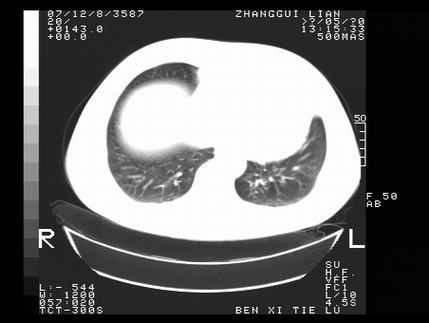

标题: CT10818:男,73,TB病史,现病史肺炎及直肠CANCER术后 [打印本页]

标题: CT10818:男,73,TB病史,现病史肺炎及直肠CANCER术后

左侧中央型肺癌伴阻塞性肺炎\\不张,左侧前上纵隔亦增宽,建议上传纵隔窗除外淋巴结转移.

考虑:左侧中央型肺癌伴阻塞性肺炎,纵隔淋巴结转移。

1)考虑为:左侧中央型肺癌伴阻塞性肺炎,纵隔淋巴结转移。2)双侧少量胸腔积液。3)心包积液。

左侧中央型肺癌伴阻塞性肺炎,纵隔淋巴结转移。

考虑左侧中央型肺癌伴阻塞性肺炎,纵隔淋巴结转移。